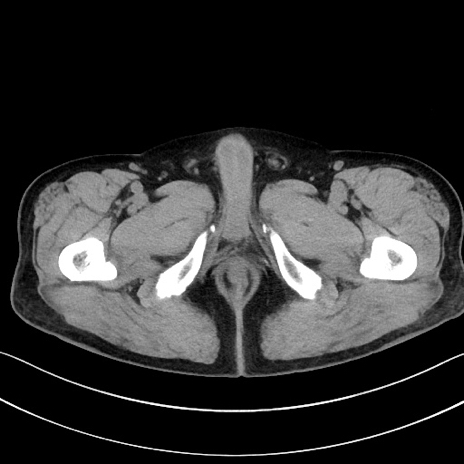

症例15(横断像)

【症例】70歳代男性

【主訴】腹痛

【現病歴】今朝から腹痛あり。全体的に痛い。特に左上の方。排ガスが今日はない。冷や汗が出る。

【既往歴】直腸癌術後

【身体所見】左側腹部〜上腹部に圧痛あり。腹膜刺激症状明らかなではない。軽度反跳痛。左下腹部に術後瘢痕あり。

【データ】WBC 7700、CRP 0.02